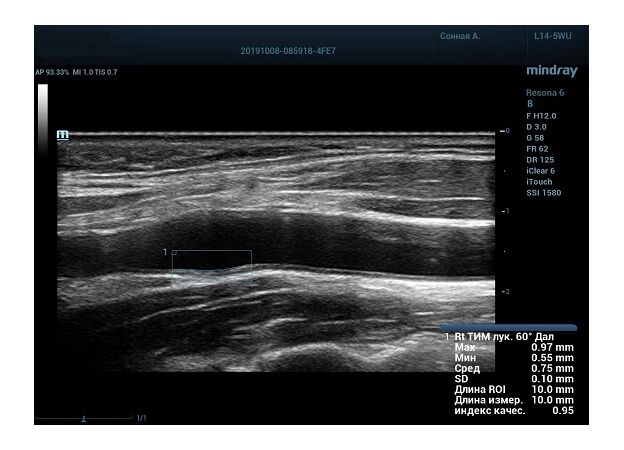

На сегодняшний день измерение IMT происходит автоматическим путем при использовании функции AUTO-IMT. Необходимо указать прибору зону интереса, стандартной длиной (1 см), в которой происходит отслеживание кромок и выдача максимального, среднего и минимального значения. УЗИ аппараты компании Mindray среднего, экспертного и премиального класса снабжены данной функцией и позволяют контролировать не только полученные значения, но и оценить точность измерения кромки в конкретной зоне по индексу качества. Используя индекс качества, легко решить, можно ли использовать полученное значение.

Форма отчета стала удобной: в единой таблице сводятся измерения левых и правых артерий, указываются все значения с автоматическим расчетом общего среднего показателя. Если один из показателей измерения резко выбивается и считается недостоверным – его можно исключить из расчета.